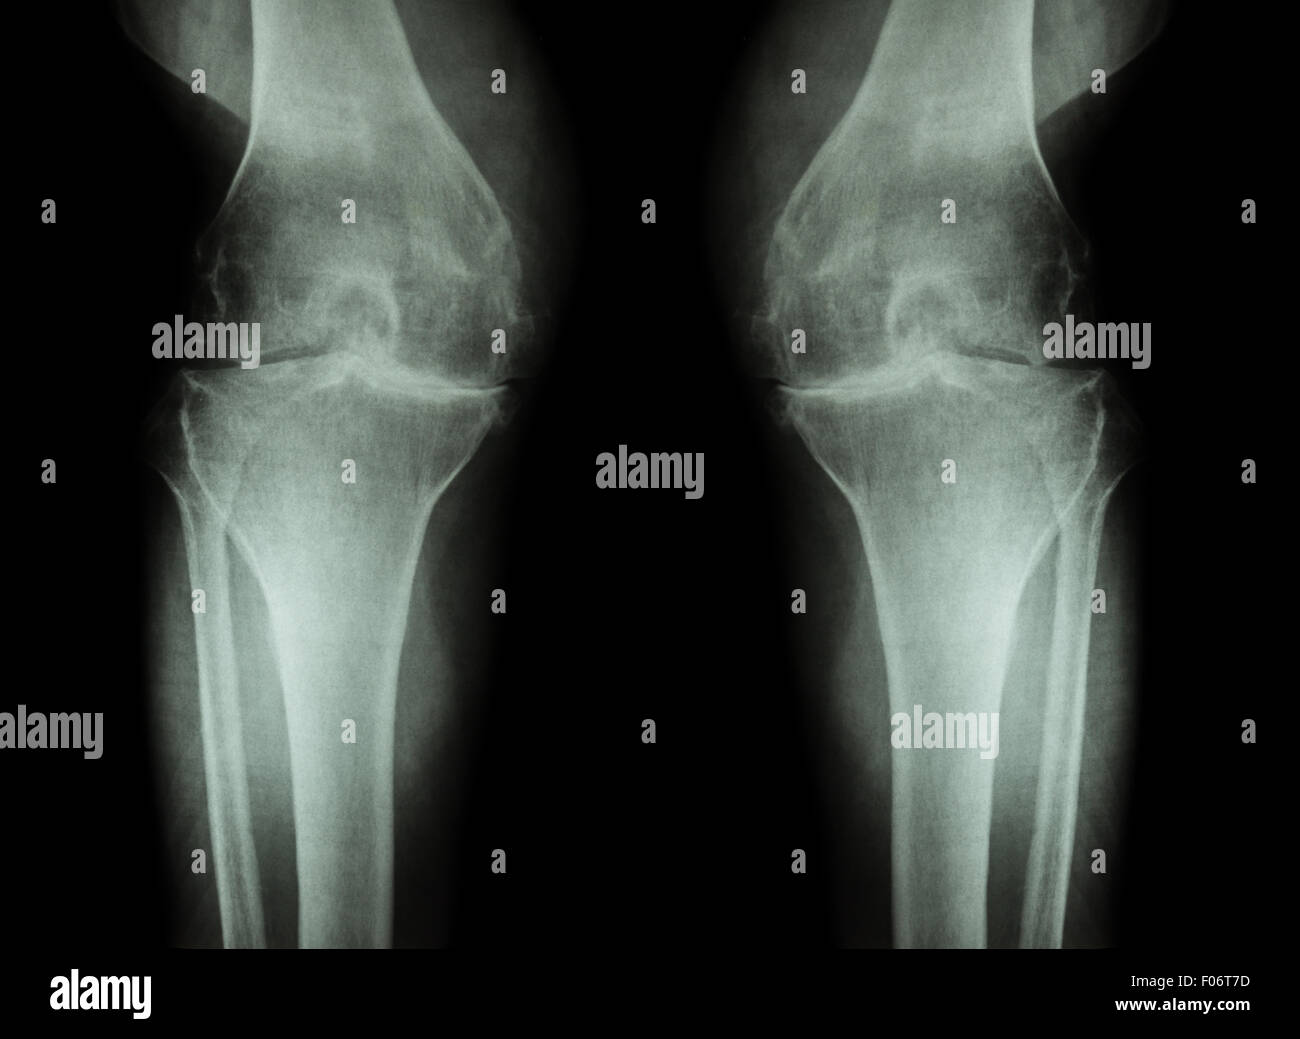

L'ARTHROSE DU GENOU Arthrose du genou ( ) ( Film x-ray à la fois avec l'arthrite du genou d'articulation du genou : articulation du genou espace ) ( Médecine et Sc Banque D'Imageshttps://www.alamyimages.fr/image-license-details/?v=1https://www.alamyimages.fr/photo-image-l-arthrose-du-genou-arthrose-du-genou-film-x-ray-a-la-fois-avec-l-arthrite-du-genou-d-articulation-du-genou-articulation-du-genou-espace-medecine-et-sc-86202577.html

L'ARTHROSE DU GENOU Arthrose du genou ( ) ( Film x-ray à la fois avec l'arthrite du genou d'articulation du genou : articulation du genou espace ) ( Médecine et Sc Banque D'Imageshttps://www.alamyimages.fr/image-license-details/?v=1https://www.alamyimages.fr/photo-image-l-arthrose-du-genou-arthrose-du-genou-film-x-ray-a-la-fois-avec-l-arthrite-du-genou-d-articulation-du-genou-articulation-du-genou-espace-medecine-et-sc-86202577.htmlRFF06T7D–L'ARTHROSE DU GENOU Arthrose du genou ( ) ( Film x-ray à la fois avec l'arthrite du genou d'articulation du genou : articulation du genou espace ) ( Médecine et Sc

L'ARTHROSE DU GENOU Arthrose du genou ( ). Film x-ray deux genou ( vue avant ) show spatial commun étroit ( perte de cartilage ) , osteophy Banque D'Imageshttps://www.alamyimages.fr/image-license-details/?v=1https://www.alamyimages.fr/photo-image-l-arthrose-du-genou-arthrose-du-genou-film-x-ray-deux-genou-vue-avant-show-spatial-commun-etroit-perte-de-cartilage-osteophy-87802628.html

L'ARTHROSE DU GENOU Arthrose du genou ( ). Film x-ray deux genou ( vue avant ) show spatial commun étroit ( perte de cartilage ) , osteophy Banque D'Imageshttps://www.alamyimages.fr/image-license-details/?v=1https://www.alamyimages.fr/photo-image-l-arthrose-du-genou-arthrose-du-genou-film-x-ray-deux-genou-vue-avant-show-spatial-commun-etroit-perte-de-cartilage-osteophy-87802628.htmlRFF2RN44–L'ARTHROSE DU GENOU Arthrose du genou ( ). Film x-ray deux genou ( vue avant ) show spatial commun étroit ( perte de cartilage ) , osteophy